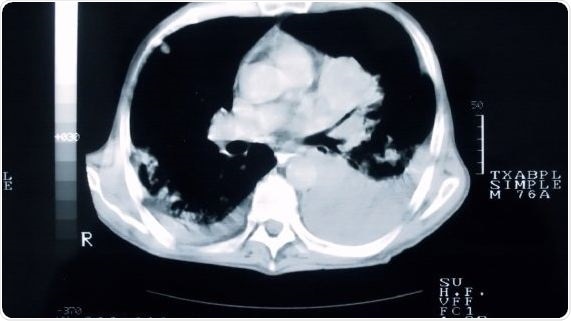

Smokers who undergo a CT scan of their lungs are more likely to quit than those who don’t, concludes a trial led by Cardiff University.

The UK Lung Cancer Screening (UKLS) pilot trial is the first to assess the feasibility, cost-effectiveness and behavioral impact of lung cancer screening, using a single low-dose CT screen on a high-risk population in the UK.